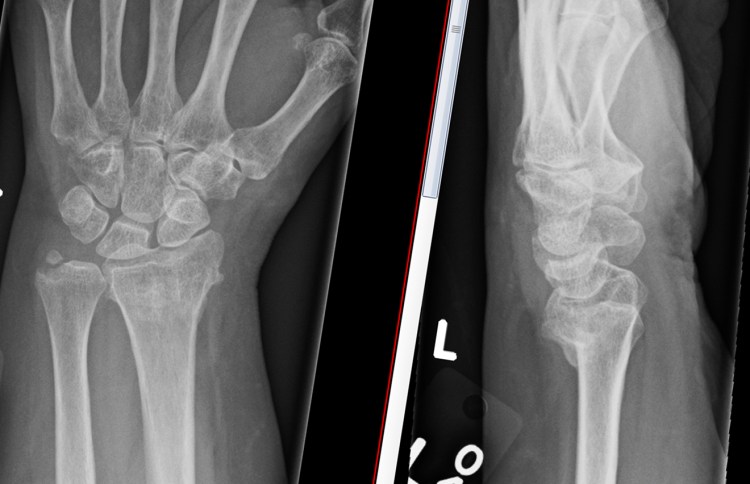

Malunion is the name used when a bone has healed in a position that is different to the normal position of the bone. This is one of the ‘classical‘ complications of a fracture of the distal radius, and is extremely common, affecting around 30% of people who have this injury. A malunion of the distal radius will make the wrist look a different shape to the other wrist.

People may be disappointed by the appearance of their wrist following a malunion, because it looks so different to the other side. As well as looking different, the wrist is usually a slightly different colour, with some swelling, but these two findings are normal after any wrist fracture.

Following treatment for a fracture of the distal radius, all patients usually have to overcome some residual pain, swelling and stiffness in the wrist. Additional disappointment in the appearance of the wrist can focus people psychologically to avoid using the hand and wrist normally. Although swelling around the wrist continues to diminish over the months following a fracture, the basic shape of the wrist will remain the same as the position it has healed in – it never returns to normal. People tend to associate a different shape of the wrist with a poor outcome, but the shape of the wrist does not usually play a major part in any symptoms of functional loss, which is more likely to be a problem with the position of the joint between the two forearm bones at the wrist.